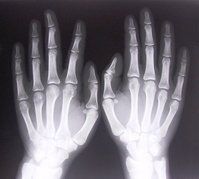

Post hoc analyses of (FUTURE 5) 541 active PsA pts Rx w/ secukinumab shows NO radiographic progression through 2 years of SEC was assoc with achieving LDA at Week 104. https://t.co/IyCsJOm9PS https://t.co/PgDKanxaNU